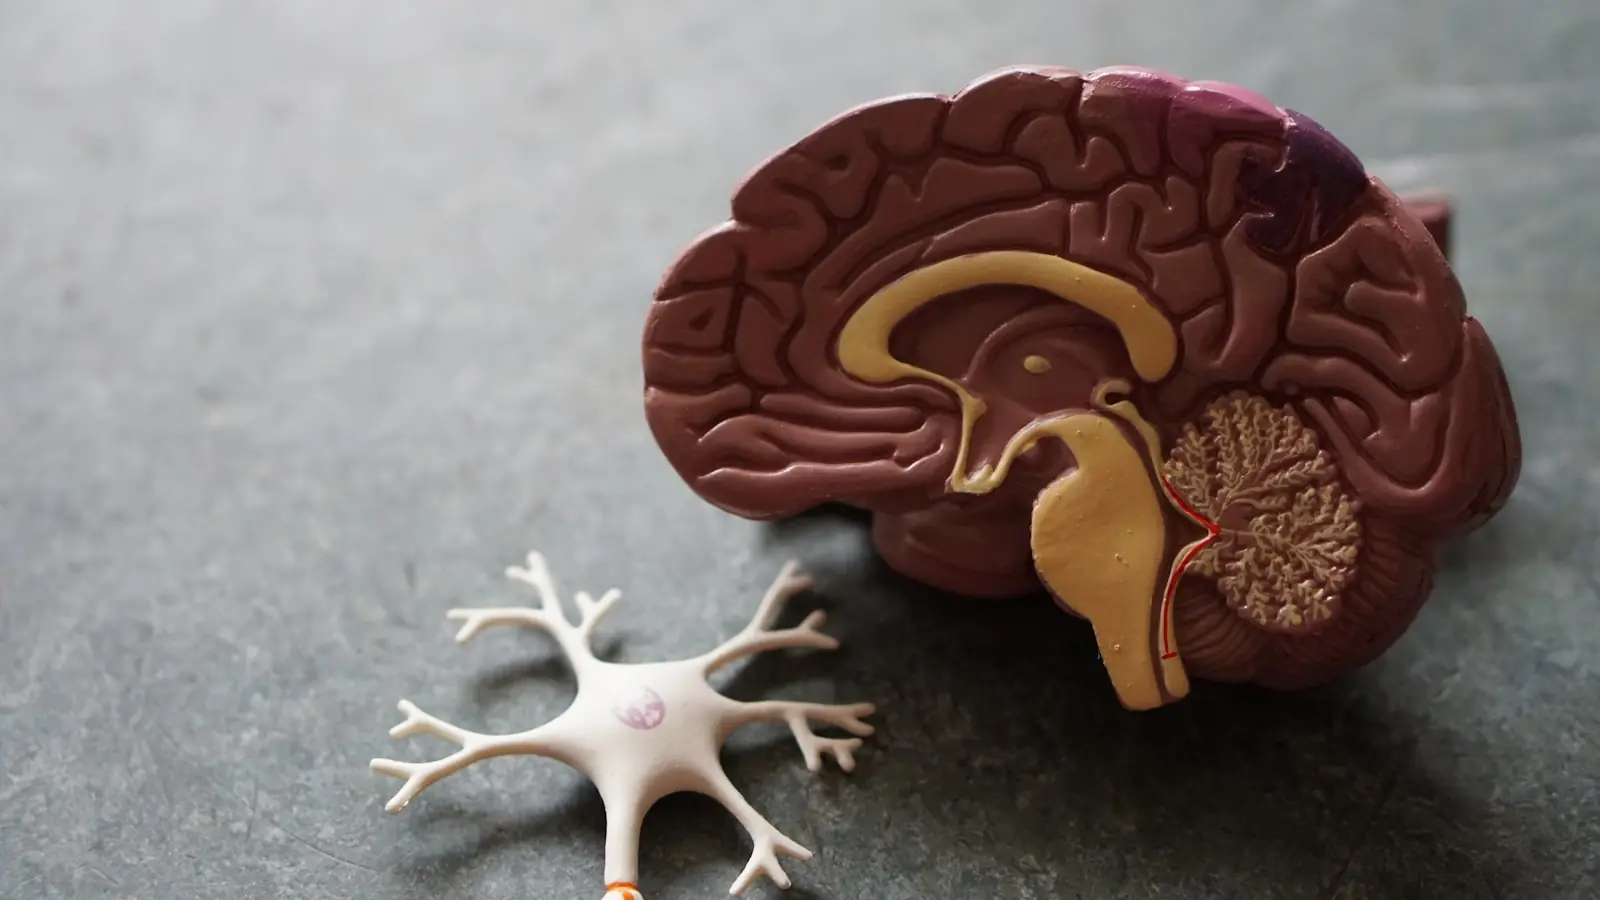

Cientistas identificaram uma proteína chamada FTL1 que parece acelerar o envelhecimento no hipocampo — a parte do cérebro ligada à memória — em roedores mais velhos. Quando presente em níveis altos, ela pode fazer com que cérebros jovens apresentem características típicas do envelhecimento.

Mas há esperança: ao reduzir essa proteína em camundongos idosos, os pesquisadores observaram uma melhora significativa na atividade cerebral e nas funções cognitivas. Manipulações em laboratório sugerem que é possível prevenir efeitos negativos do envelhecimento cerebral.

O estudo, publicado na Nature Aging, abre caminho para terapias que possam não apenas retardar, mas até reverter parte dos danos cognitivos associados à velhice, com potencial impacto no combate a doenças como Alzheimer.